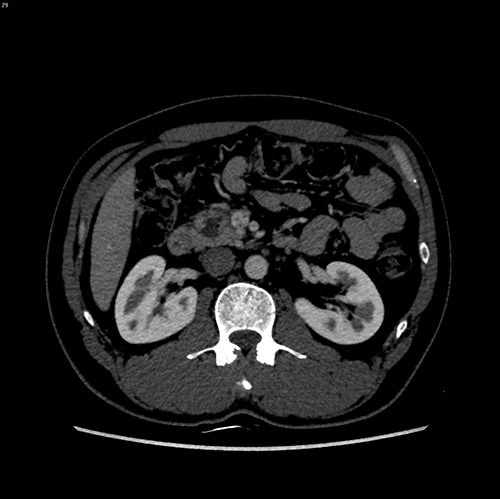

肿块型慢性胰腺炎----胰十二指肠切除